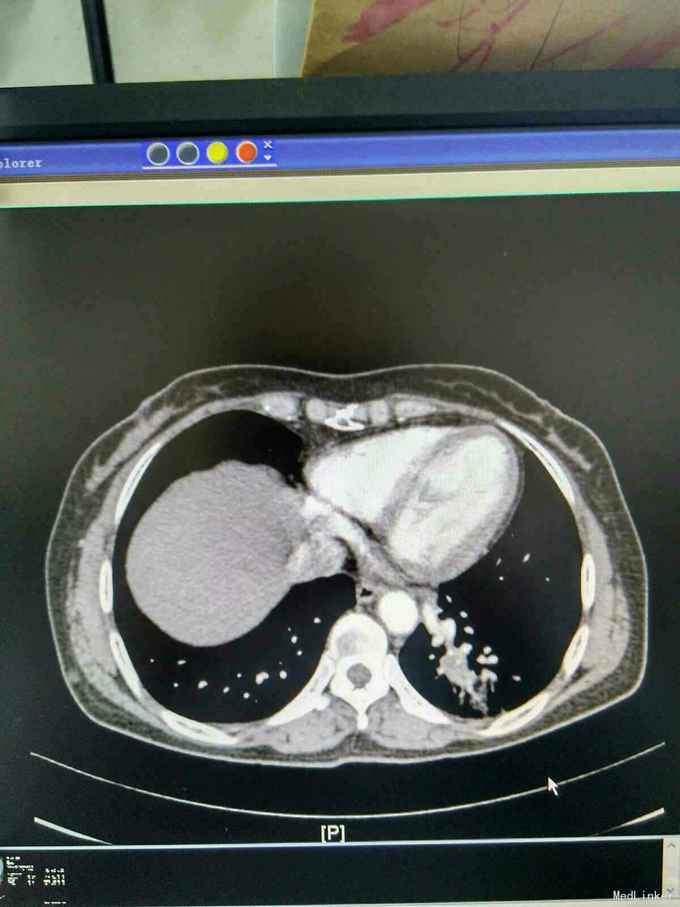

患者44岁女性,以“咳嗽咳痰间断咯血1月余”为主诉入院,入院前1月余不明显诱因出现咳嗽,呈阵发性非刺激性,咳黄白痰,每日五六口,间断咯血,色鲜红,每次10到50毫升不等,余无特殊不适,就诊当地医院摄胸部ct提示左下肺炎,予抗感染止咳化痰止血处理后症状反复,半月前复查胸部CT提示肺部阴影较前增大。

查体,神志清楚,浅表淋巴结未触及肿大,左下肺呼吸音减弱,可闻及少许湿性啰音。外院胸片示,左下肺斑片状实变阴影。

我院胸部ct增强,见左下肺病灶内见一异常供血血管,发自降主动脉,病灶周围见斑片状磨玻璃影。诊断为左肺下叶肺隔离症,转外科治疗。

患者外院胸部ct提示左下肺块影,原计划行ct引导下肺穿次活检术,我院胸部ct增强后发现,病灶为肺隔离症。遂转外科行左下肺切除术。